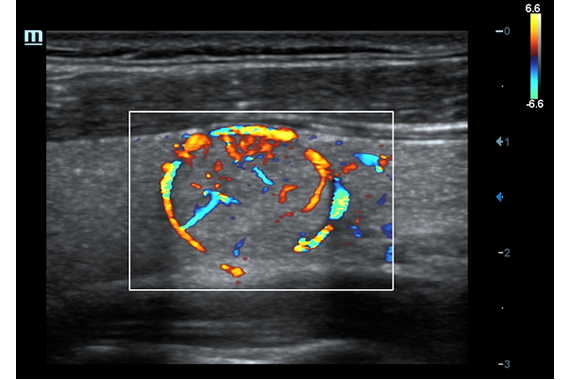

• HR Flow - режим отображения кровотока с высоким временным и пространственным разрешением для точной и однородной визуализации сосудов, в том числе самых мелких.

• HR Flow - режим отображения кровотока с высоким временным и пространственным разрешением для точной и однородной визуализации сосудов, в том числе самых мелких